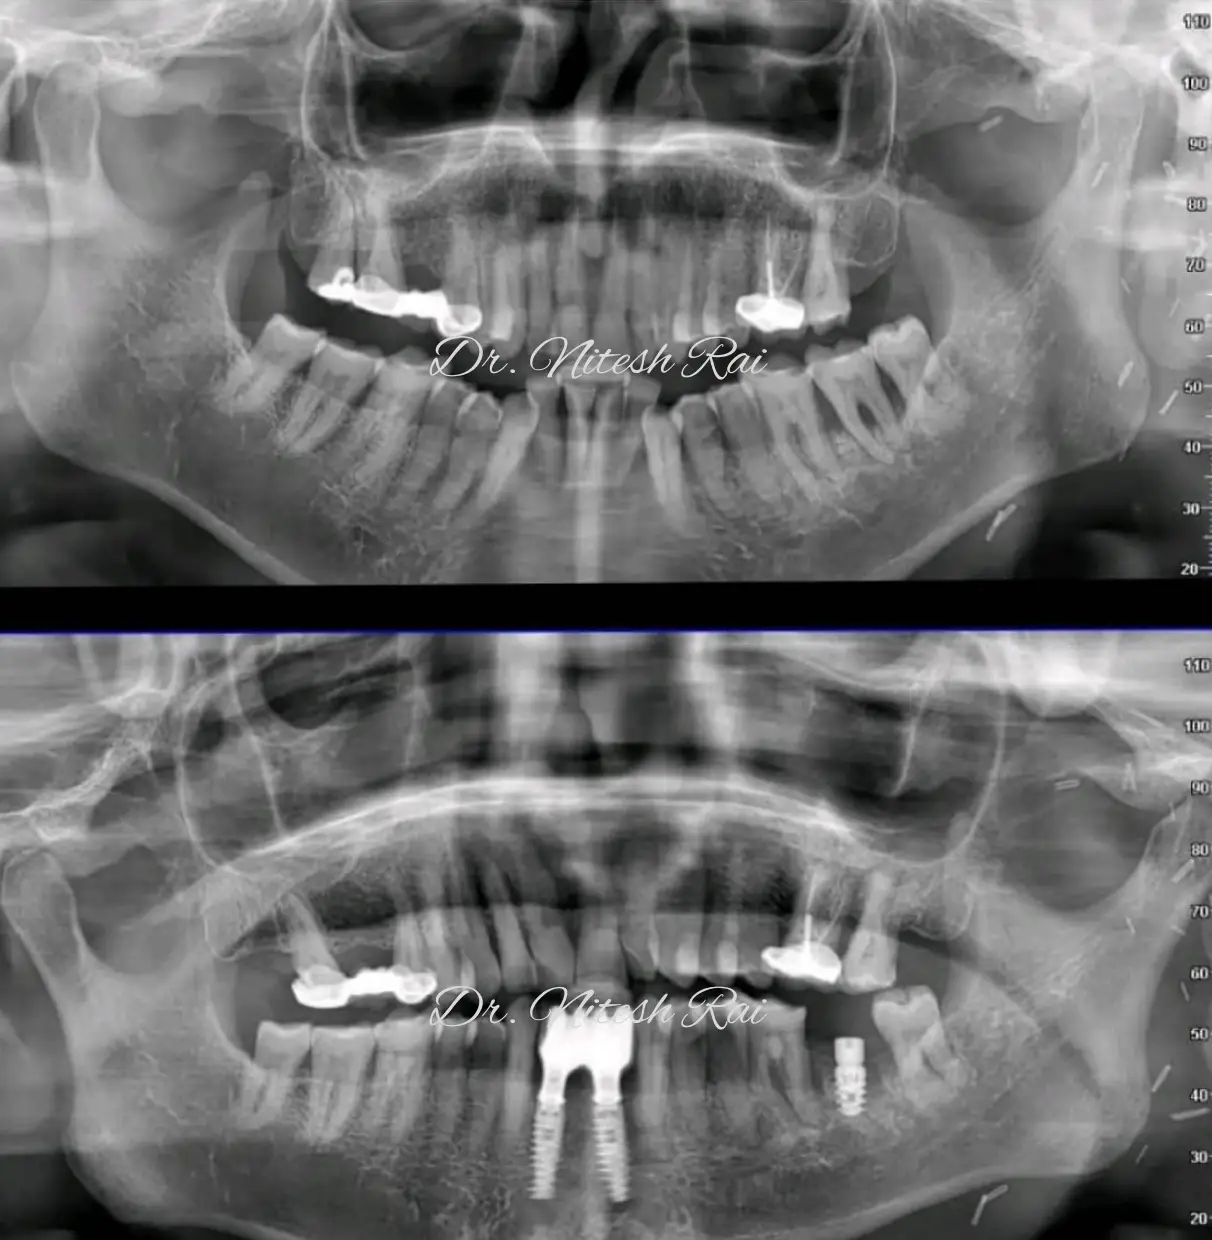

Dr Nitesh Rai, specializes in replacement of teeth with complete dentures, removable partial dentures, fixed partial dentures and Implants.

He has been actively involved in providing implant treatment for over two decades. He is also a committed academician, educating dental students and has been associated with Krishnadevaraya college of Dental sciences, Bengaluru as a Senior Professor, PG Guide and teacher in the Department of Prosthodontics, Crown and Bridge and Implant.